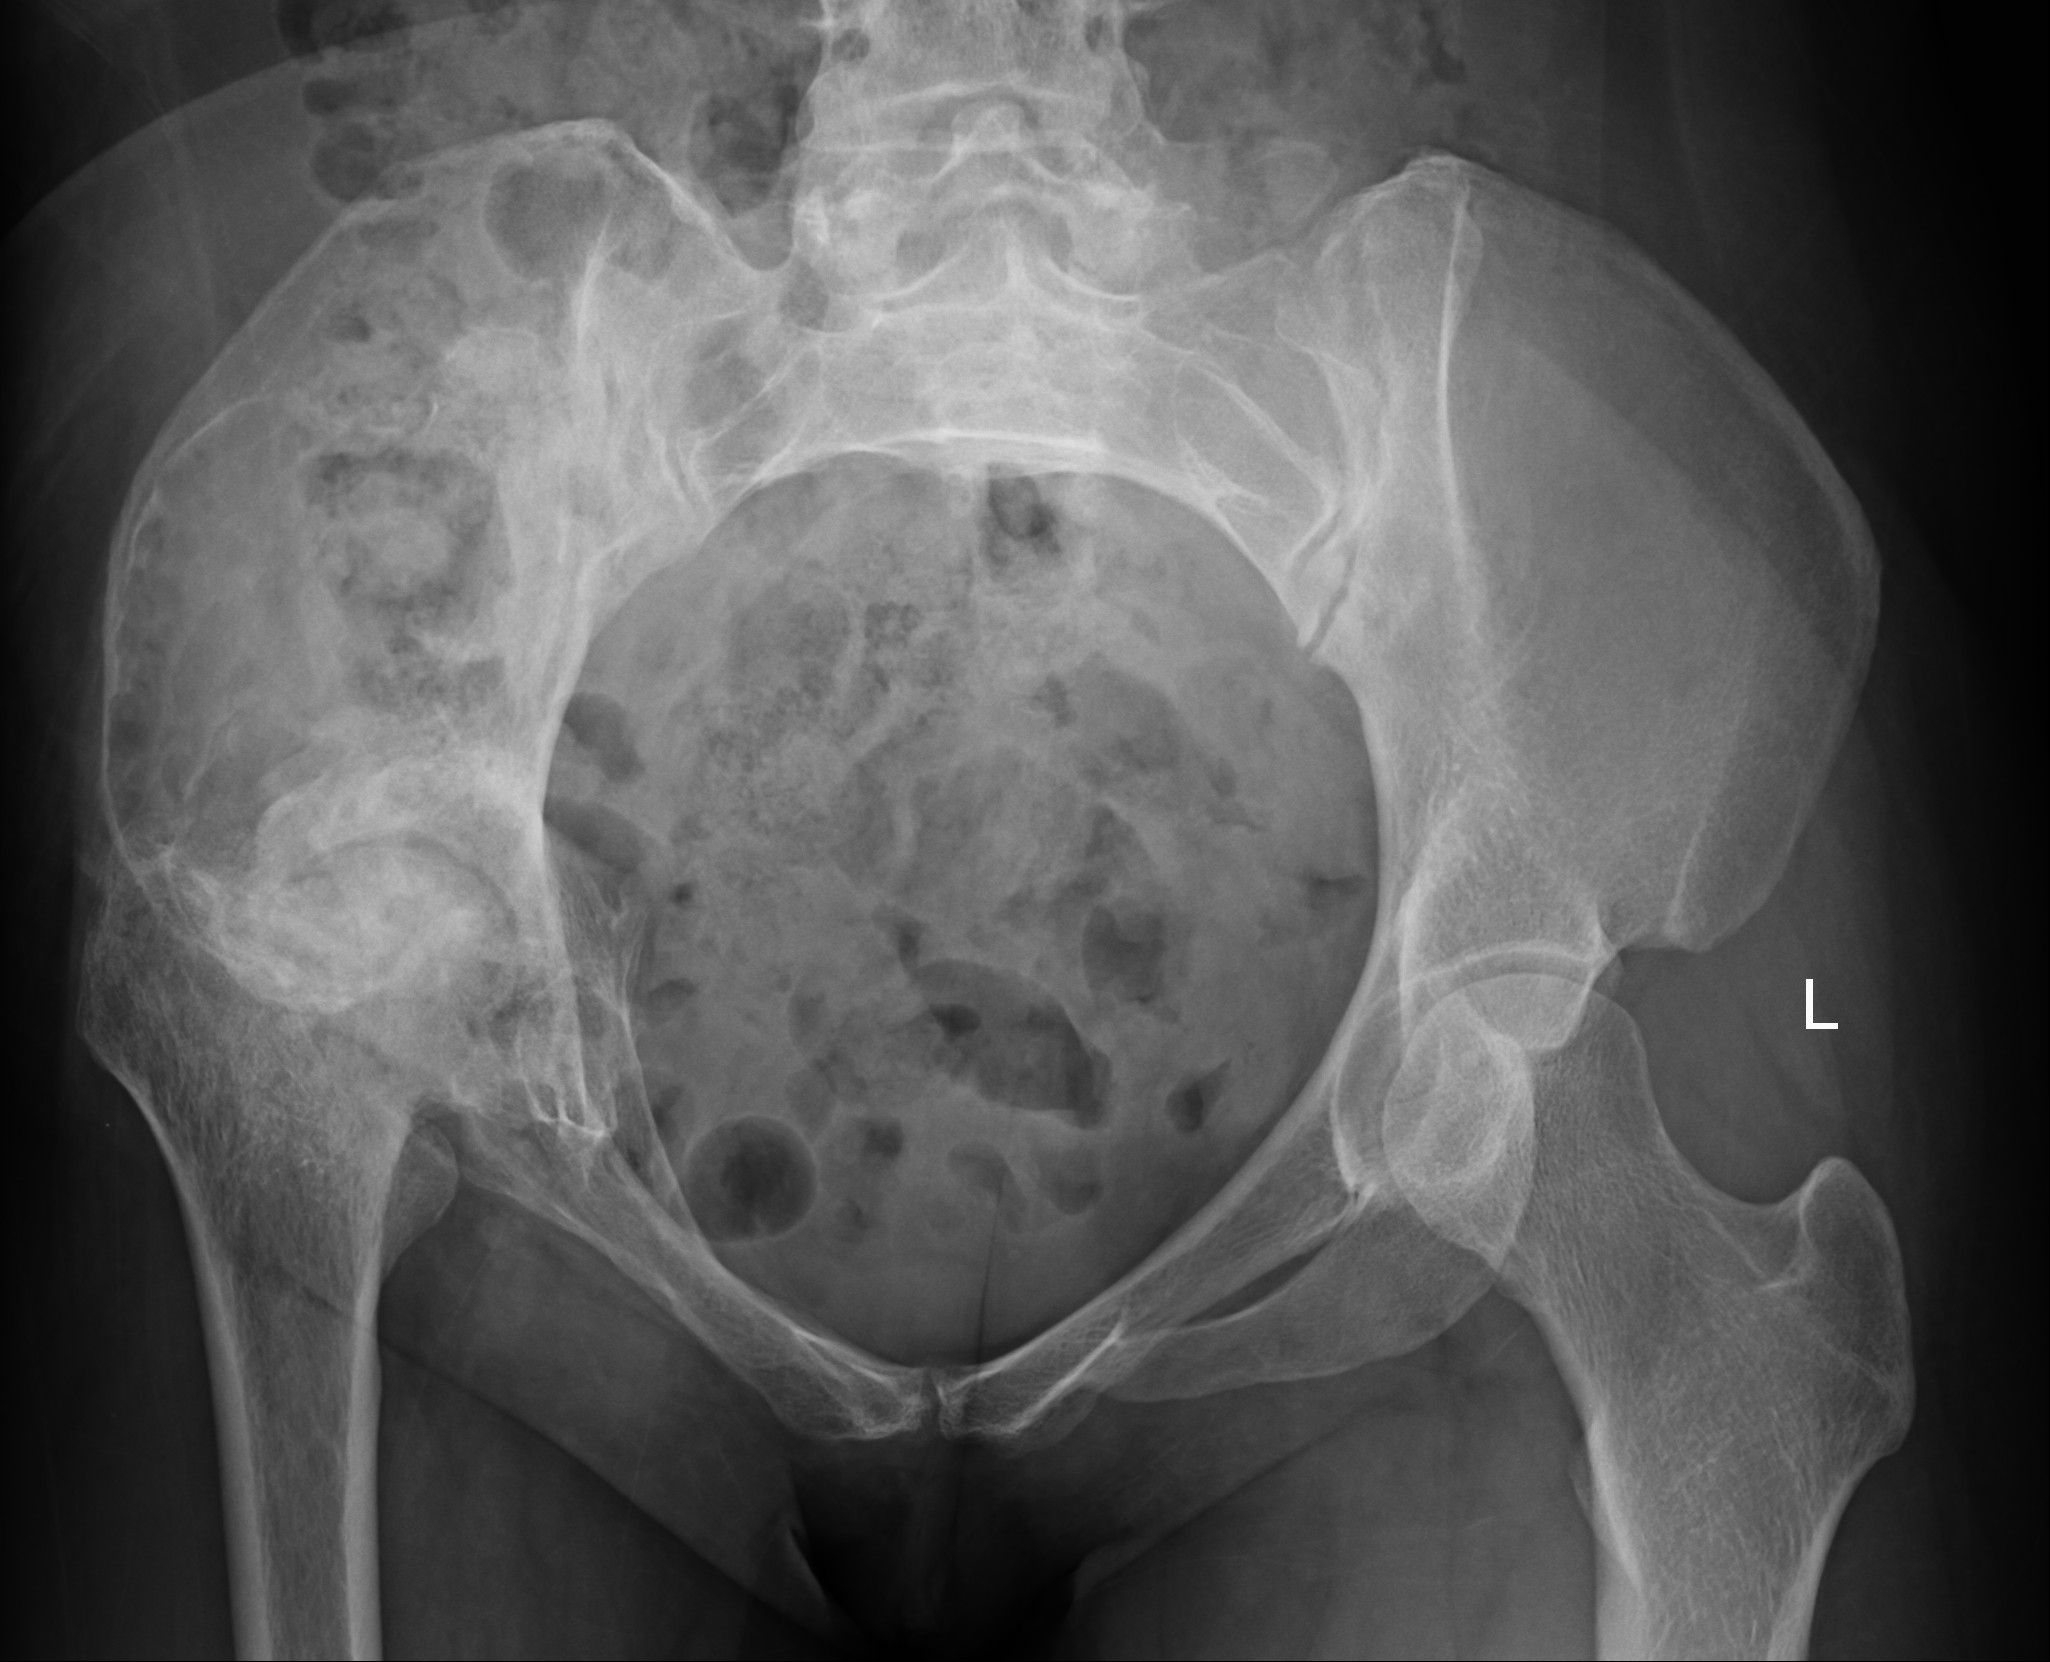

Laboratory examinations revealed no significant abnormalities. The pelvic plain film showed that the joint space of the right hip joint was narrowed, the femoral neck was shortened, and there was ischemic necrosis of the femoral head. Radiographs revealed a large expansile radiolucent lesion, with cortical erosion of the right iliac bone (Figure 1). Computed tomography (CT) revealed significant osteolytic destruction in the right iliac wing, along with a mass in the surrounding tissue. Irregular cystic degeneration areas were observed within it. The mass, measuring approximately 10.3 cm × 6.2 cm × 7.8 cm, had an indistinct boundary with muscle tissue (Figure 2). Magnetic resonance imaging (MRI) revealed an iliac mass showing hypo intensity.

Figure 2

Figure 2. The CT scan demonstrated right ilium bone destruction, a surrounding ~10.3×6.2×7.8 cm soft tissue mass with irregular cysts, and an unclear muscle tissue boundary.